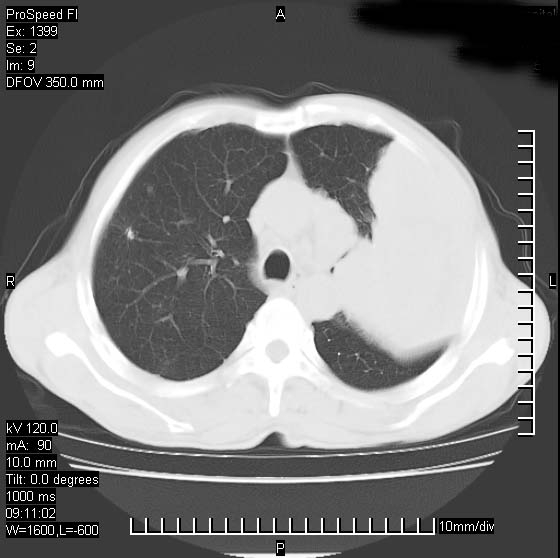

以下是引用卜一在2007-1-19 9:55:00的发言:[br]左肺沿胸膜下巨大肿块影,边缘呈分叶征,纵隔内见肿大淋巴结,右肺内另见一不规则结节影 .考虑:左肺周围性肺癌伴纵隔 右肺内转移.

以下是引用rgsyyf在2007-1-19 11:05:00的发言:[br]左肺上叶见形态不规则巨大软组织肿块影,边缘呈分叶征,纵隔内隆突下见肿大淋巴结,右肺内另见一不规则结节影 .考虑:左肺周围性肺癌伴纵隔即右肺内转移.